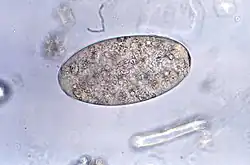

| Fasciolopsis buski egg | |

Adults produce over 25,000 eggs every day; these take up to seven weeks to mature and hatch at 27–32 °C. Immature, unembryonated eggs are discharged into the intestine and stool. In two weeks, eggs become embryonated in water, and after about seven weeks, tiny parasitic organisms called miracidia hatch from the eggs, which then go on to invade a suitable snail intermediate host. Several species in the genera Segmentina and Hippeutis serve as intermediate hosts. In the snail the parasite undergoes several developmental stages (sporocysts, rediae, and cercariae). The cercariae are released from the snail and encyst as metacercariae on aquatic plants such as water chestnut, water caltrop, lotus, bamboo, and other edible plants. The mammalian final host becomes infected by ingesting metacercariae on the aquatic plants. After ingestion, the metacercariae encyst in the duodenum in about three months and attach to the intestinal wall. There they develop into adults (20 to 75 mm by 8 to 20 mm) in approximately three months, remaining attached to the intestinal wall of the mammalian hosts (humans and pigs). The adults have a life span of about one year.[7]

Examination of stool samples microscopically to identify parasite eggs can aid in the diagnosis of this parasite. However, due to intermittent egg shedding, multiple stool samples may be necessary for an accurate diagnosis. The WHO recommends the Kato-Katz technique as the method of choice for fascioliasis diagnosis attending to its ease of use and reproducibility, and its enhanced sensitivity compared with the observation of eggs in fresh faeces. Enzyme-linked immunosorbent assay (ELISA) or other serological tests can also help identify specific antibodies against Fasciolopsis buski antigens in the blood. In some cases, imaging techniques like ultrasound or endoscopy might also be used to visualize the flukes within the intestines.[8]